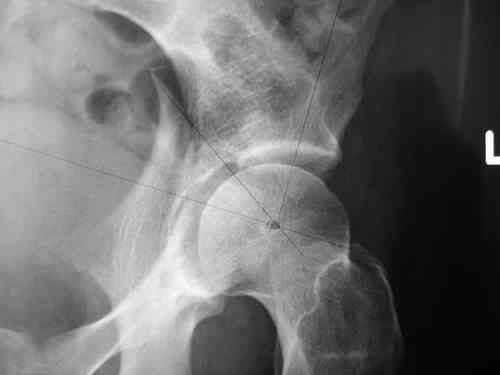

Дорогой Андрей. Мы имеем дело с комбинированной (ротационно и вертикально) нестабильностью таза со смещением правого гнемипелвиса. При таких переломах, фиксация только переднего полукольца вне зависимости от метода фиксации, как уже было сказано Djoldas Kuldjanov, M.D., не может создать адекватной фиксации. И перелом пластины был вполне ожидаемым после активизации пациента. Смещение сохраняется, и по-видимому не 2 см., а все 4, если не более. Разница всего (+2 см) по конечностям как вы указываете, скорее скомпенсировано позвоночником и протезом. Дополнительные снимки или КТ исследование помогли бы уточнить степень смещения с точностью до мм., выявить перелом поперечного отростка пятого поясничного позвонка, или помимо разрыва правого крестцово-подвздошного сочленения выявить перелом боковой массы крестца справа и т.д. При возможности, конечно, все это желательно сделать. Но мало что изменится с практической точки зрения, т.к. задача - это низведение репозиция и надежная фиксация правого гемипелвиса. Учитывая плачевный опыт стержневого аппарата, давность травмы совершенно очевидно, что поставленная задача достижима при открытой репозиции и одномоментной фиксации переднего полукольца с артродезированием правого крестцово-подвздошного сустава. Операция выполняется в положении больного на здоровом боку или полубоку из расширенного трансоссального подвздошно-пахового доступа с переходом на лонное сочленение доступом по Pfannenstiel. Указанный доступ обеспечивает подход к крестцово-подвздошному сочленению как спереди так и сзади. После артродезирования выполняется синтез лонного сочленения. Клинический пример

Пациентка С.26 лет. Травма за 6 месяцев до поступления

Укорочение правой нижней конечности до 10см